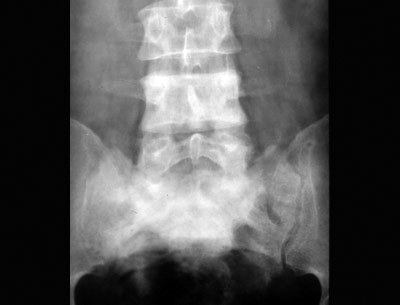

Los cambios radiográficos son patognomónicos, y suelen llevar al diagnóstico. La Fig. 80-2 muestra un húmero; la Fig. 80-3 una vértebra, la Fig. 80-4 una pelvis, y la Fig. 80-5 un cráneo afectados por la enfermedad de Paget; la Fig. 80-6 es el estudio tomográfico del mismo cráneo.

Fig. 80-3. La 4ª vértebra lumbar es radiodensa. A veces las vértebras pagéticas son más grandes que las vecinas no afectadas, lo que ayuda en el diagnóstico diferencial de lesiones vertebrales osteocondensantes.